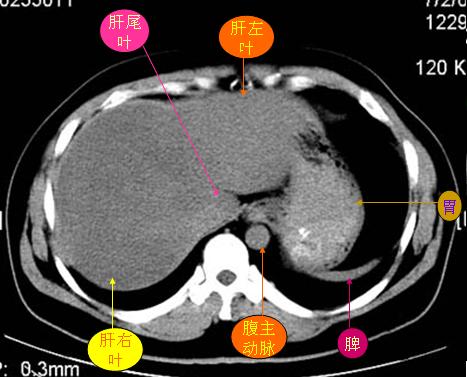

腹部ct解剖与基本病变